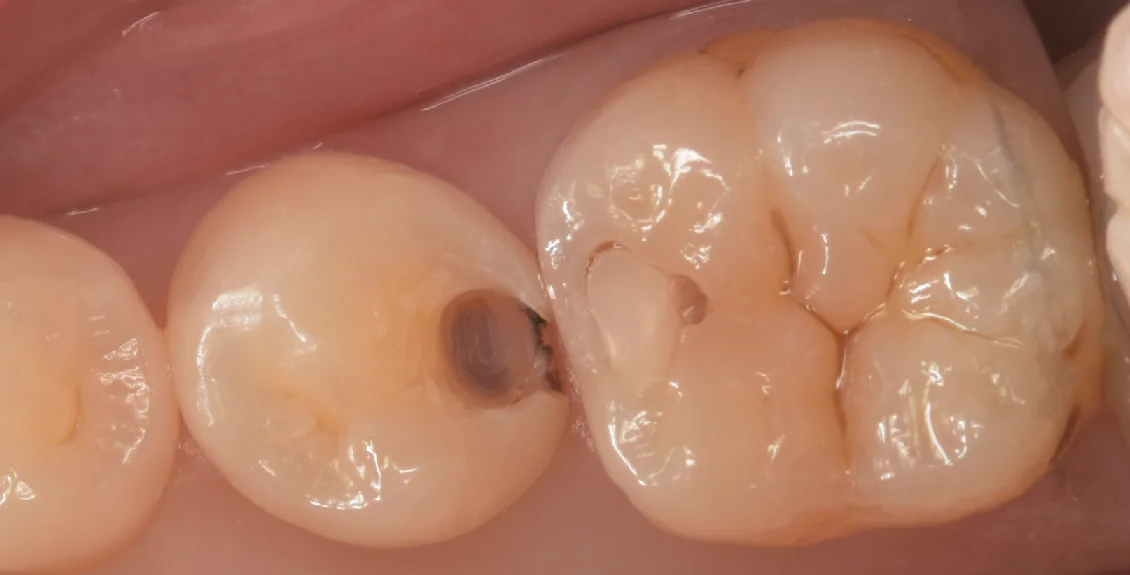

まずは術前からです。

元々詰めてあった白い詰め物の部分がかけてそこから虫歯になってしまっています。

元の詰め物自体の適合はさほど悪くはないのですが・・・

詰め物を大体除去してみると・・・

ご覧の通り、内部に虫歯が残存している状態でした。

残存しているのか、新しく発生したのかの判断が難しいケースもありますが、今回は新しく入ってきた虫歯と既存の虫歯の部分がつながっていなかったため純粋な取り残しがあったと思われます。